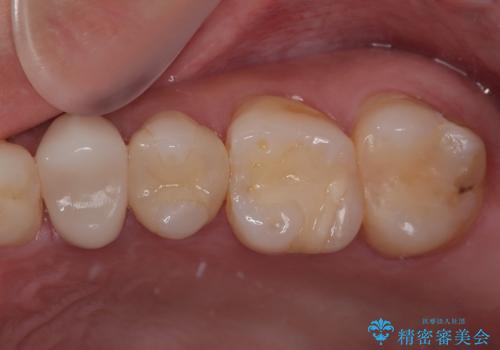

- プラスチックの詰め物が取れたとのことで来院された患者様です。神経の状態を検査し、正常な状態を確認してから残っている自分の歯の量を考慮しセラミックインレーにて修復しました。

拡大鏡視野下でコンポジットレジン、虫歯の除去を行い、セラミックインレーに適した形に整えました。

歯と歯茎の間に圧排糸と言われる糸を入れてシリコーン印象材にて精密な型どりをしました。

セラミックインレーの装着時には、唾液の侵入を防ぐために、ラバーダム防湿を行いました。